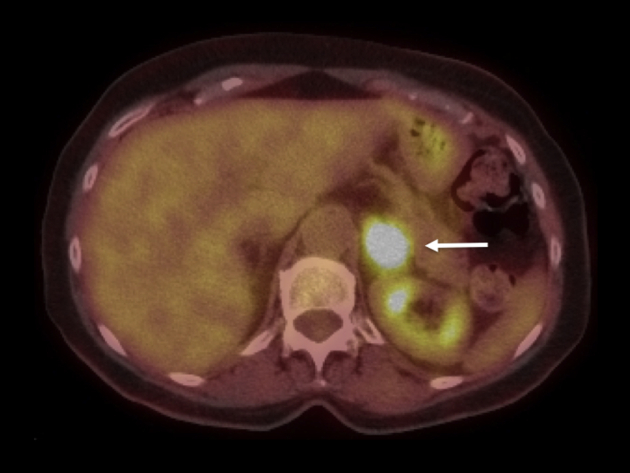

Figure 2.

Positron Emission Tomography/CT imaging displaying avid FDG uptake (11.3 SUV) in the adrenal mass (arrows). No other pathologic FDG uptake was noted elsewhere in the body.